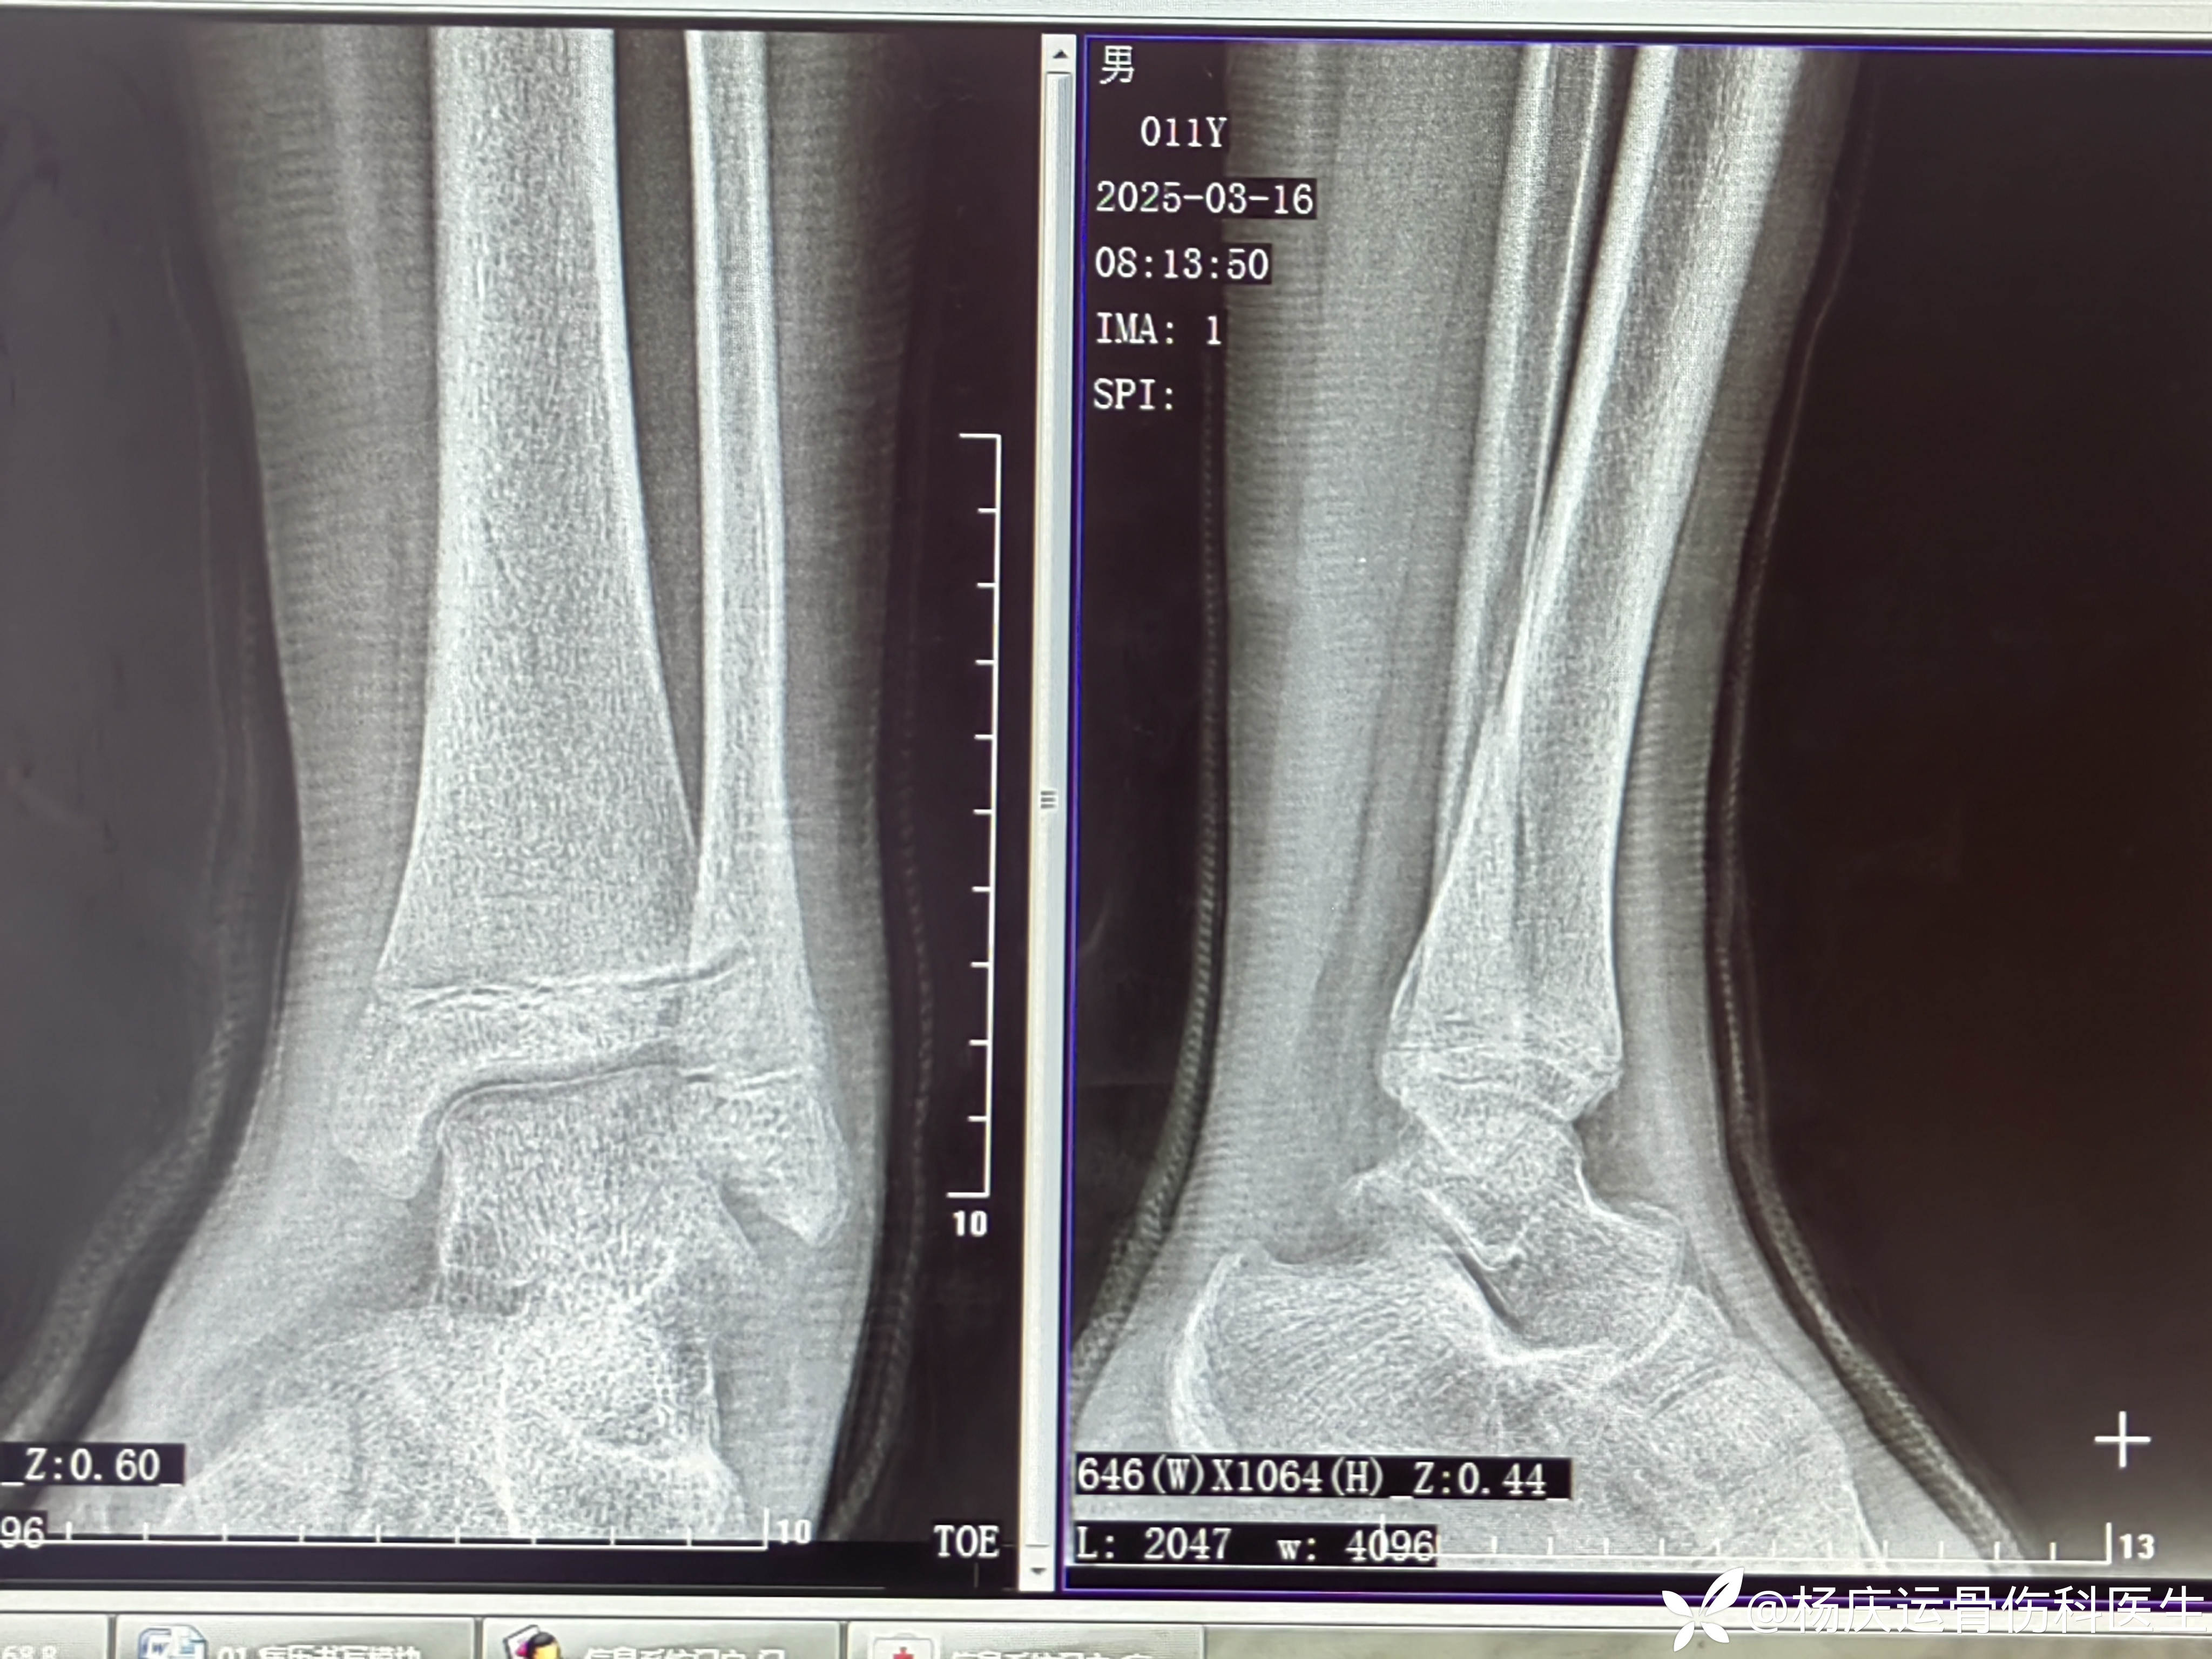

18天复查

1个月复查